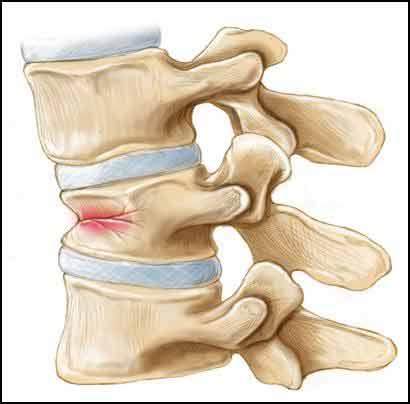

Le fratture vertebrali osteoporotiche vengono definite da “compressione” (Fig. 2) poiché conducono al collasso del corpo vertebrale allorquando le forze che devono sostenere eccedono la loro resistenza.

Fig. 2 Frattura da compressione